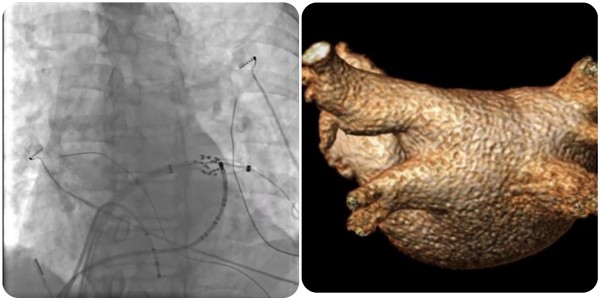

近日,皇冠足球投注网 (简称皇冠足球网 )心血管内科团队完成广西首批三维标测系统指导下经皮导管脉冲电场消融术(即CardiPulse脉冲电场消融系统上市后广西首批应用),为一名阵发性房颤患者进行了房颤脉冲电场消融治疗,成功帮助患者恢复正常心律。

在夏文豪的指导下,皇冠足球投注网 心血管内科心律失常介入团队为患者制定了个性化诊疗方案,并联系介入导管中心、重症医学科、心胸外科、手术麻醉中心做好应急预案,为手术全程保驾护航。手术仅2小时,消融过程中患者心律转为正常,肺静脉即刻隔离,术后恢复良好,目前已康复出院。

脉冲电场消融(Pulsed Field Ablation,PFA)利用短时程、高电压的多个电脉冲释放消融能量,可在细胞膜上产生不可逆的纳米级微孔,导致细胞死亡,可用于房颤导管消融,实现肺静脉隔离。